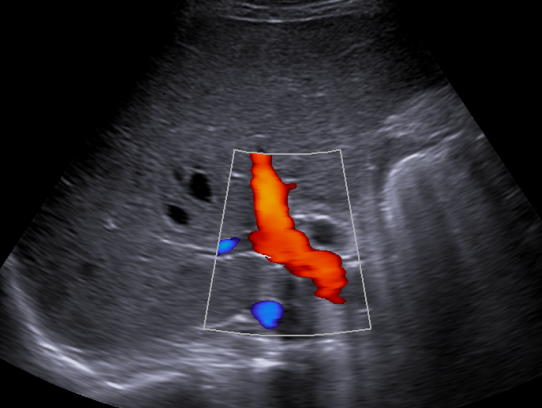

Karaciğerin ana toplardamarı olan portal venin renkli Doppler Ultrason görüntüsü.

Doppler ultrasonografi, ses dalgaları yardımıyla dokudaki veya damarlardaki kan akımının gösterilmesi yardımıyla damarsal hastalıkların tanısında kullanılan bir tanı yöntemidir.